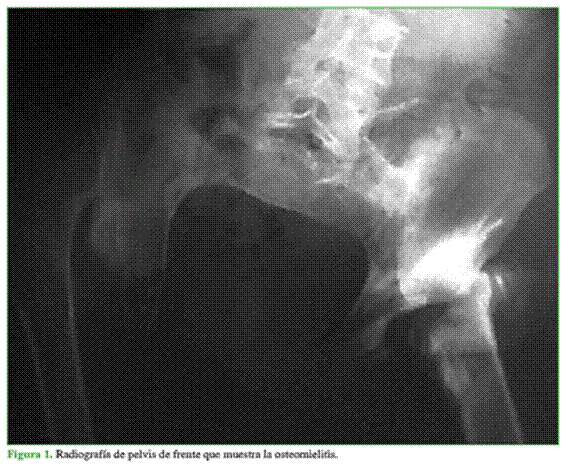

Hombre de 25 años que había sufrido un accidente de moto cinco años atrás. La lesión le produjo una fractura a nivel de D10 y un cuadro de paraplejia con nivel sensitivo compatible con la lesión. Su estado neurológico se clasificó como Frankel A. Los malos cuidados higiénicos le provocaron escaras múltiples en piernas, sacro y trocánteres, que obligaron a realizar varios procedimientos quirúrgicos, inclusive la amputación infrarrotuliana de ambas piernas (Figura 1). Este cuadro irreversible continuó evolucionando y finalizó con el desarrollo de una osteomielitis pélvica masiva que requirió la colocación de una talla vesical permanente y una cirugía de Hartman (colostomía).